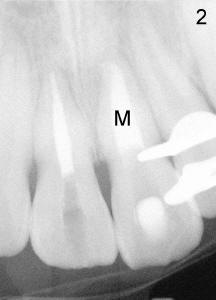

One month later (July 12, 2011), RCT was finished with gutta percha for #8, and white MTA (Dentsply, Tulsa) for #9 (M in Fig.2).  Approximately 8 mm of MTA was left in the canal.  Due to insurance coverage, composite build up was finished for #8, but not for #9.